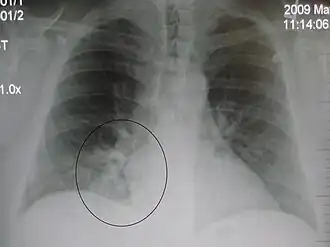

Occult pneumonia

Occult pneumonia is a pneumonia that is not observable directly by the eye, but can only be shown indirectly, especially by radiography. Occult pneumonia can be made visible by chest X-rays.